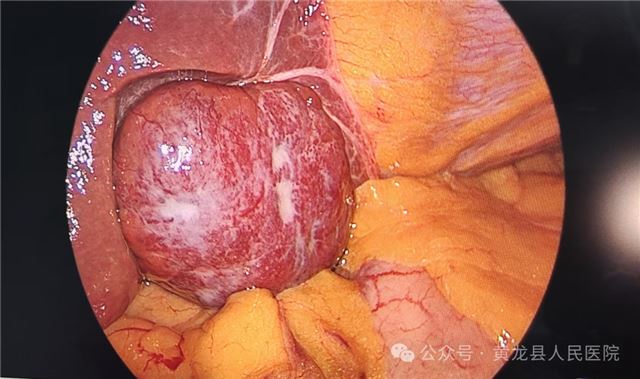

2,术中

术中探查

术后切除部分肝组织约4.5×4cm